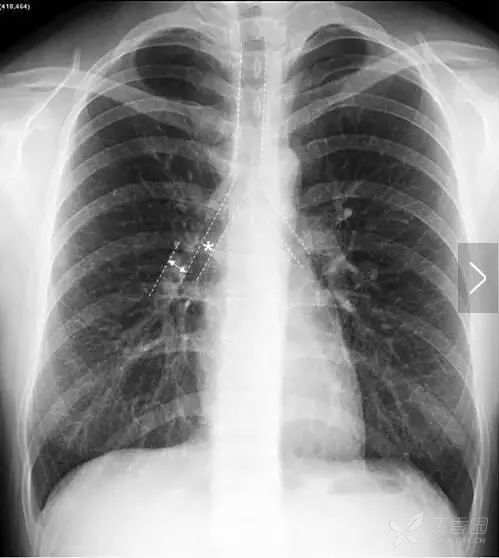

肩胛骨 如果投照时体位标准,上肢内旋充分,则肩胛骨应当位于肺野之外。否则肩胛骨将重叠于上肺野偏外的区域,呈与胸壁平行的条带状高密度影。此时可能会被误认为是肺内病变。仔细观察可见肩胛骨影从肺内向肺外延伸,即可与肺内病变区别。

上图摄片时双上肢未充分内旋,导致双侧肩胛骨大部分重叠于双肺中上肺野中外带,导致相应肺野条带状密度增高。白色箭头标示右侧肩胛骨内侧缘,向肺外延续。左侧肩胛骨情况类似。